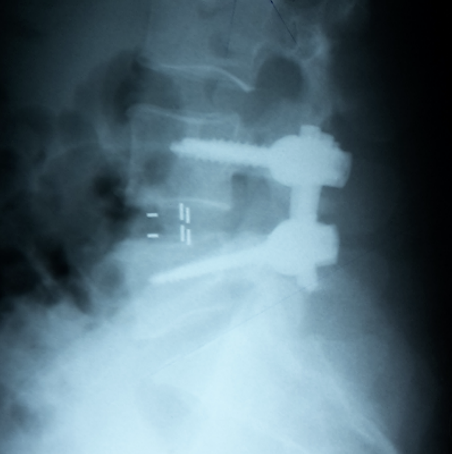

Radiografii din incidenţa anteroposterioară şi laterală ale unui pacient cu spondilolistezis L4-L5 ce a suferit o intervenţie chirurgicală de decompresie şi fuziune intercorporeala posterioară cu şuruburi pediculare şi două cage-uri (TLIF).

Radiografii din incidenţa anteroposterioară şi laterală ale unui pacient cu spondilolistezis L4-L5 ce a suferit o intervenţie chirurgicală de decompresie şi fuziune intercorporeala posterioară transforaminala cu şuruburi pediculare şi cage PEEK (PLIF)